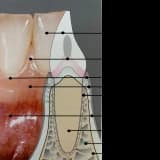

Kanama, kızarıklık ve şişlik dişeti hastalığının çarpıcı belirtileridir. Dişeti hastalığında; çene kemiğinin erimesi sonucu dişlerin sallanmasına kadar geçen süreçte en rahatsız edici dolayısıyla da en dikkat çekici belirti kanamadır. Bu nedenle de dişeti kanaması çok ciddiye alınmalı ve görüldüğü anda takip edilerek doktora gidilmelidir.